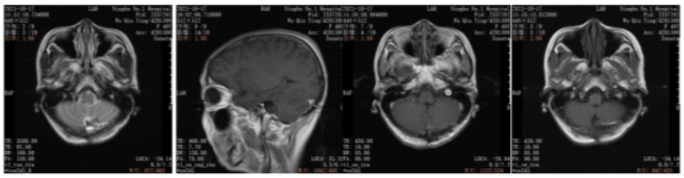

2019年10月乳腺彩超(术前):左乳实性占位(BI-RADS 4c级)。左腋下淋巴结肿大,考虑转移。

图1.乳腺彩超